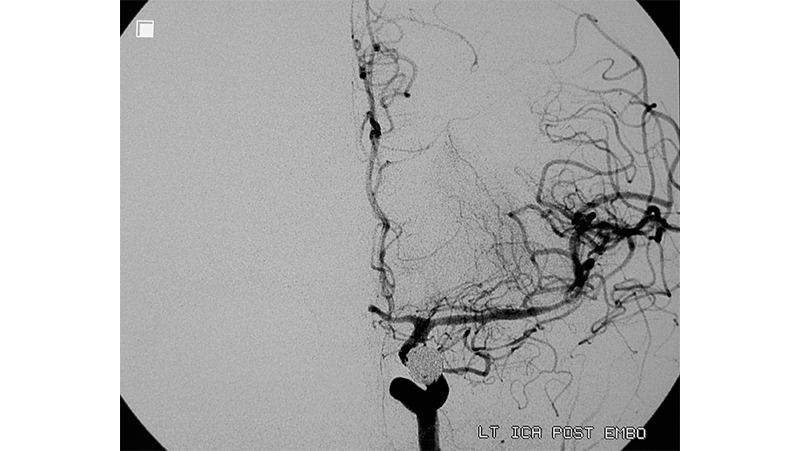

Εικόνα 4: Χορήγηση εκ νέου ενδαρτηριακά 100mg παπαβερίνης.